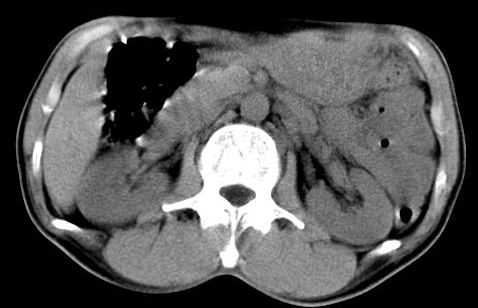

病人资料:男,50岁,上腹部隐痛,消瘦乏力,有乙肝病史二十余年,b超提示肝内内占位。

由于是基层医院,机器速度跟不上,增强效果差,请各位老师也看看!

肝右叶后段低密度灶,增强受机器限制,特点不明显,无等密度充填及周围强化,结合病人乙肝史20年,首先考虑肝癌。

肝右后叶占位,增强时期没抓好,特点不明显,结合病史首先考虑原发性肝癌

肝右叶后下内侧段占位:肝癌可能性大。胰腺占位可能,病人没有空腹准备。

肝右叶后段占位,肝癌可能性大。下腔静脉无移位。肾上腺占位不支持?

考虑肝右叶后下内侧段占位:肝癌可能性大。增强效果很不理想。